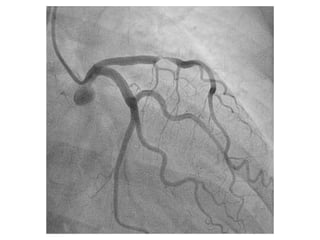

56 Jahre, weiblich

Seit 3 Tagen Herzschmerzen, zuletzt auch in Ruhe

Cholesterin

Familiäre Belastung

Übergewicht

Troponin T hs 67 pg/ml [0 -14]

EKG

Kardinal Schwarzenberg´sches Krankenhaus, Innere Medizin, Freitag 29. Juni 2012

NSTEMI - ACS 56Jahre, weiblich Seit 3 Tagen Herzschmerzen, zuletzt auch in Ruhe Cholesterin Familiäre Belastung Übergewicht Troponin T hs 67 pg/ml [0 -14] EKG Kardinal Schwarzenberg´sches Krankenhaus, Innere Medizin, Freitag 29. Juni 2012